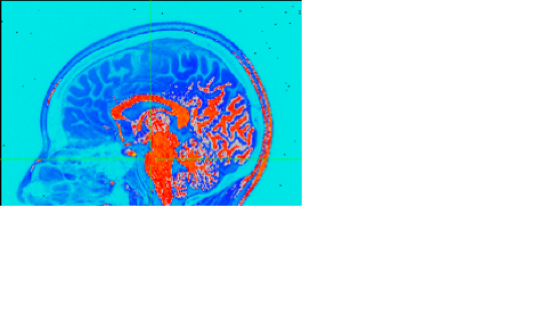

Check the box for "Pos?" so that 0 is at the bottom of this colorscale, rather than the middle.